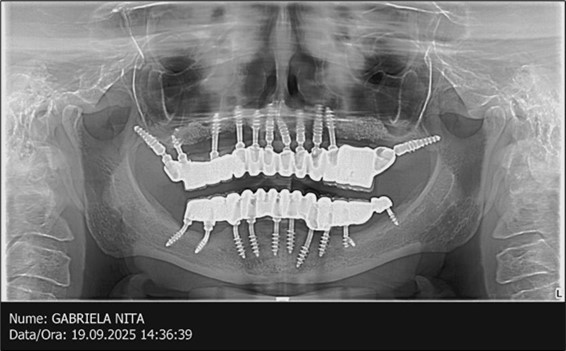

Figure 3.Panoramic pictures after removal of implants affected by peri-implantitis, extractions, alveolar crest regularization, and insertion of corticobasal and TPG implants (07.2022)

The results of rehabilitation treatment with corticobasal and compressive implants with a polished surface after the failure of two stage implants were highlighted over a period of 3 years and 3 months as being very good (Figure 14, Figure 15), with the patient completing a satisfaction survey in this regard. Certainly, it is necessary to continuemonitoring these results in the long term.